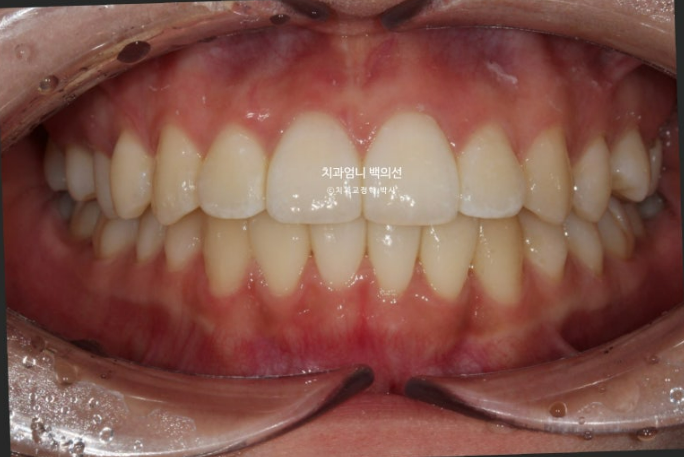

24년 9월 드디어 치료가 마무리 되었습니다.

24.09

유지장치까지 붙은 모습입니다.

총 치료기간은 9개월입니다.